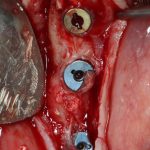

Откроем область операции и посмотрим, что там:

Вроде как, всё неплохо. Наверное, можно поставить имплантаты?

ну, или как-то так:

При этом, я хотел бы обратить ваше внимание на один важный момент. То, с чем вы сейчас работаете — не кость, в привычном нам гистолого-физиологическом понимании. Это костная мозоль вперемежку с графтом. Её свойства довольно сильно отличаются от того, что мы привыкли называть костной тканью. Поэтому при установке имплантатов соблюдайте максимальную осторожность и щадящий режим. Никаких диких торков, усилий, больших переходов между размерами фрез допускать нельзя. Будьте аккуратны.